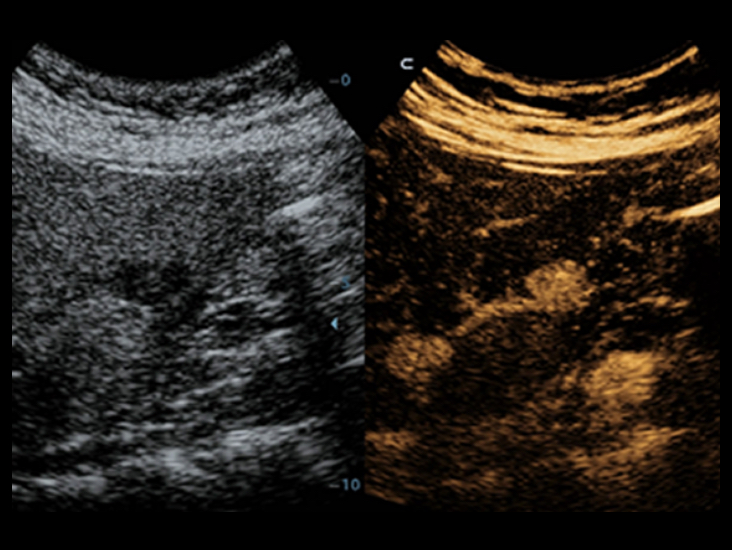

Familia de transductores optimizados: amplia gama de cobertura de aplicaciones

Gracias a una combinaciĂłn versĂĄtil de transductores, DC-40 con Full HD ofrece el mejor rendimiento equilibrado en una amplia gama de aplicaciones y produce una calidad de imagen avanzada para una gran variedad de tipos de pacientes.